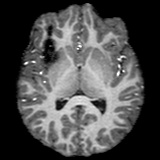

InputUNAOutputEstimatedAnomalyRefer to captionRefer to captionRefer to captionRefer to captionRefer to captionRefer to captionRefer to captionRefer to captionRefer to captionRefer to captionRefer to captionRefer to captionRefer to captionRefer to captionRefer to captionRefer to captionRefer to captionRefer to caption

Figure 5: Visualizations of directly applying UNA’s healthy anatomy reconstruction for anomaly detection. The estimated anomaly is computed as the absolute difference between diseased T1w MRI scans and UNA’s reconstructed healthy anatomy.

UNA’s ability to synthesize diseased-to-healthy anatomy naturally equips it with the potential for application to anomaly detection. To demonstrate its effectiveness, we directly use the reconstructed healthy anatomy from UNA to detect abnormalities. Specifically, we follow the standard evaluation pipeline for unsupervised anomaly detection in medical images [6, 21] and compute UNA’s anomaly estimation maps by calculating the voxel-wise absolute differences between the diseased input and the reconstructed output. The anomaly detection Dice scores are then obtained by comparing the ground truth pathology segmentations with the computed anomaly estimation maps, scaled to the range [0, 1]01[0,\,1][ 0 , 1 ] such that they represent the normalized abnormality. The same procedure is applied to other competing models.

As shown in Fig. 5, UNA’s difference maps clearly identify anomalies with varying shapes and sizes. Quantitative comparisons are provided in Tab. 3, where UNA: (i) outperforms other modality-agnostic synthesis models, and the state-of-the-art anomaly detection models; and (ii) demonstrates consistent performance across various datasets.